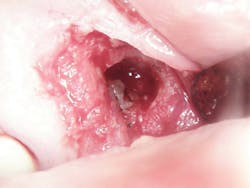

The patient, a 63-year-old female, presented for an emergency visit. She explained her situation, complaining of pain and a lump on the top-left quadrant of her mouth. After an oral evaluation and x-ray (figure 1), it was discovered that she had a large draining granuloma with swelling in the mucobuccal fold near teeth Nos. 12–14 due to a chronic periapical abscess (figure 2).